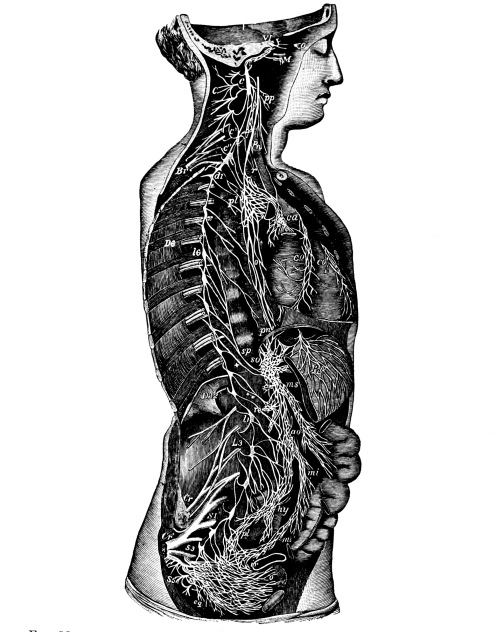

The Cerebrum, 75—The Cerebellum, 78—Pons Variolii, 78—Medulla Oblongata, 78—Spinal Cord, 79—Brain-centers, 81—Motor Tract, 82—Sensory Tract, 82—Reflex Action, 83—Cranial Nerves, 83—Spinal Nerves, 84—Brachial Plexus, 85—Sacral Plexus, 85—The Sympathetic System, 87—The Sympathetic Nerves, 87. |

| The Nervous System | 75 |